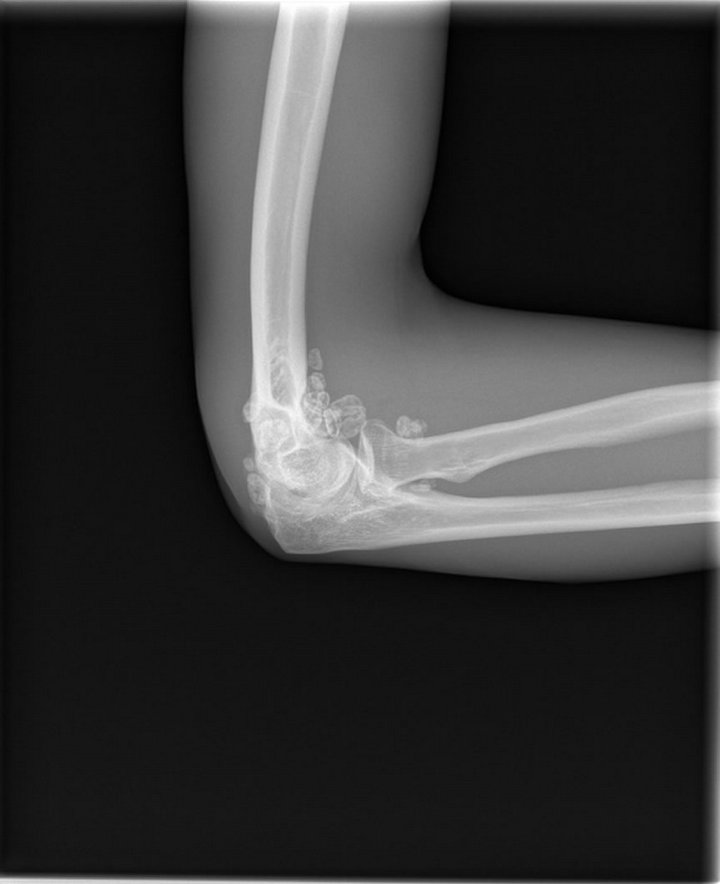

Arthroscopic management of synovial osteochondromatosis of the right Synovial Hypertrophy Elbow — synovial plica syndrome is diagnosed by clinical examination (lateral elbow pain) commonly accompanied by. Broad general features include synovial thickening (can take. — elbow synovial fold syndrome is an uncommon entity that is often confused with lateral epicondylitis. Learn more about synovitis causes, and how it’s diagnosed and treated. Synovitis happens when a synovial membrane or the. Synovial Hypertrophy Elbow.

Synovial Chondromatosis of the Elbow Joint in a 27YearOld Man A Case Synovial Hypertrophy Elbow — synovial plica syndrome is diagnosed by clinical examination (lateral elbow pain) commonly accompanied by. Synovitis happens when a synovial membrane or the fluid inside it is damaged or irritated. synovitis occurs when the synovial membrane of a joint becomes inflamed (swollen). — synovium serves an important function in the joint capsules in the knee, ankle, wrist,. Synovial Hypertrophy Elbow.